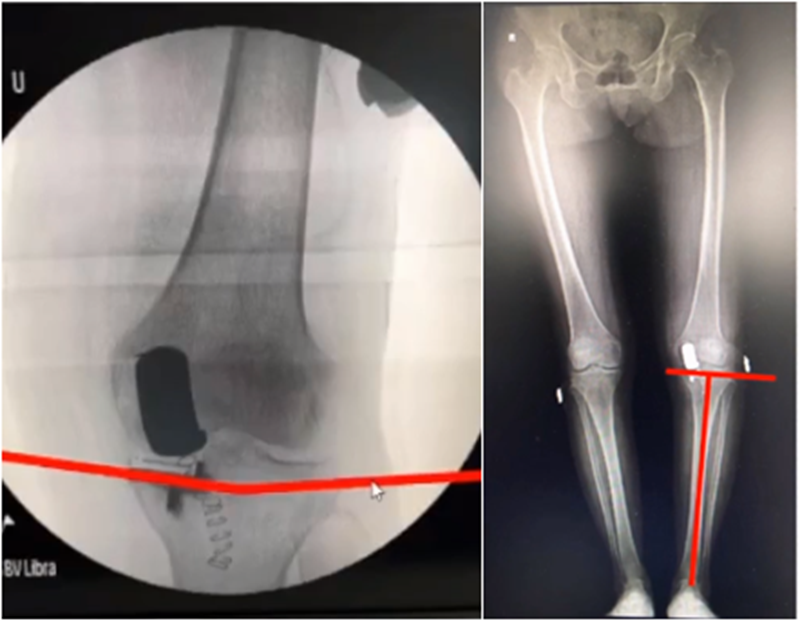

牛津单髁在假体评判中,提到股骨内外翻有10°容忍度,胫骨内外翻有5°,股骨屈伸在0-15°之间,胫骨后倾在 7-(﹣5)后倾之间。但评判标准中没有提到此种方式是基于全长片还是局部片。

文献中建议假体内外翻不大于4°,如果假体出现外翻,后倾大,会造成内侧皮质压力异常增高,增加内髁骨折风险。如果假体内翻超过5°,增加胫骨平台松动风险。

但有时候力线好,假体和外侧关节线会成角,那么对于此种情况,应如何判断假体位置内外翻定义?和外侧关节线比较,属于外翻假体;和下肢机械轴比较,属于中立位假体。

小结:判断股骨胫骨假体位置,是基于局部X线的判断,是考虑行走时关节线的方向为基准,此时内外翻不能超过5°,而不能从全长片来判断。